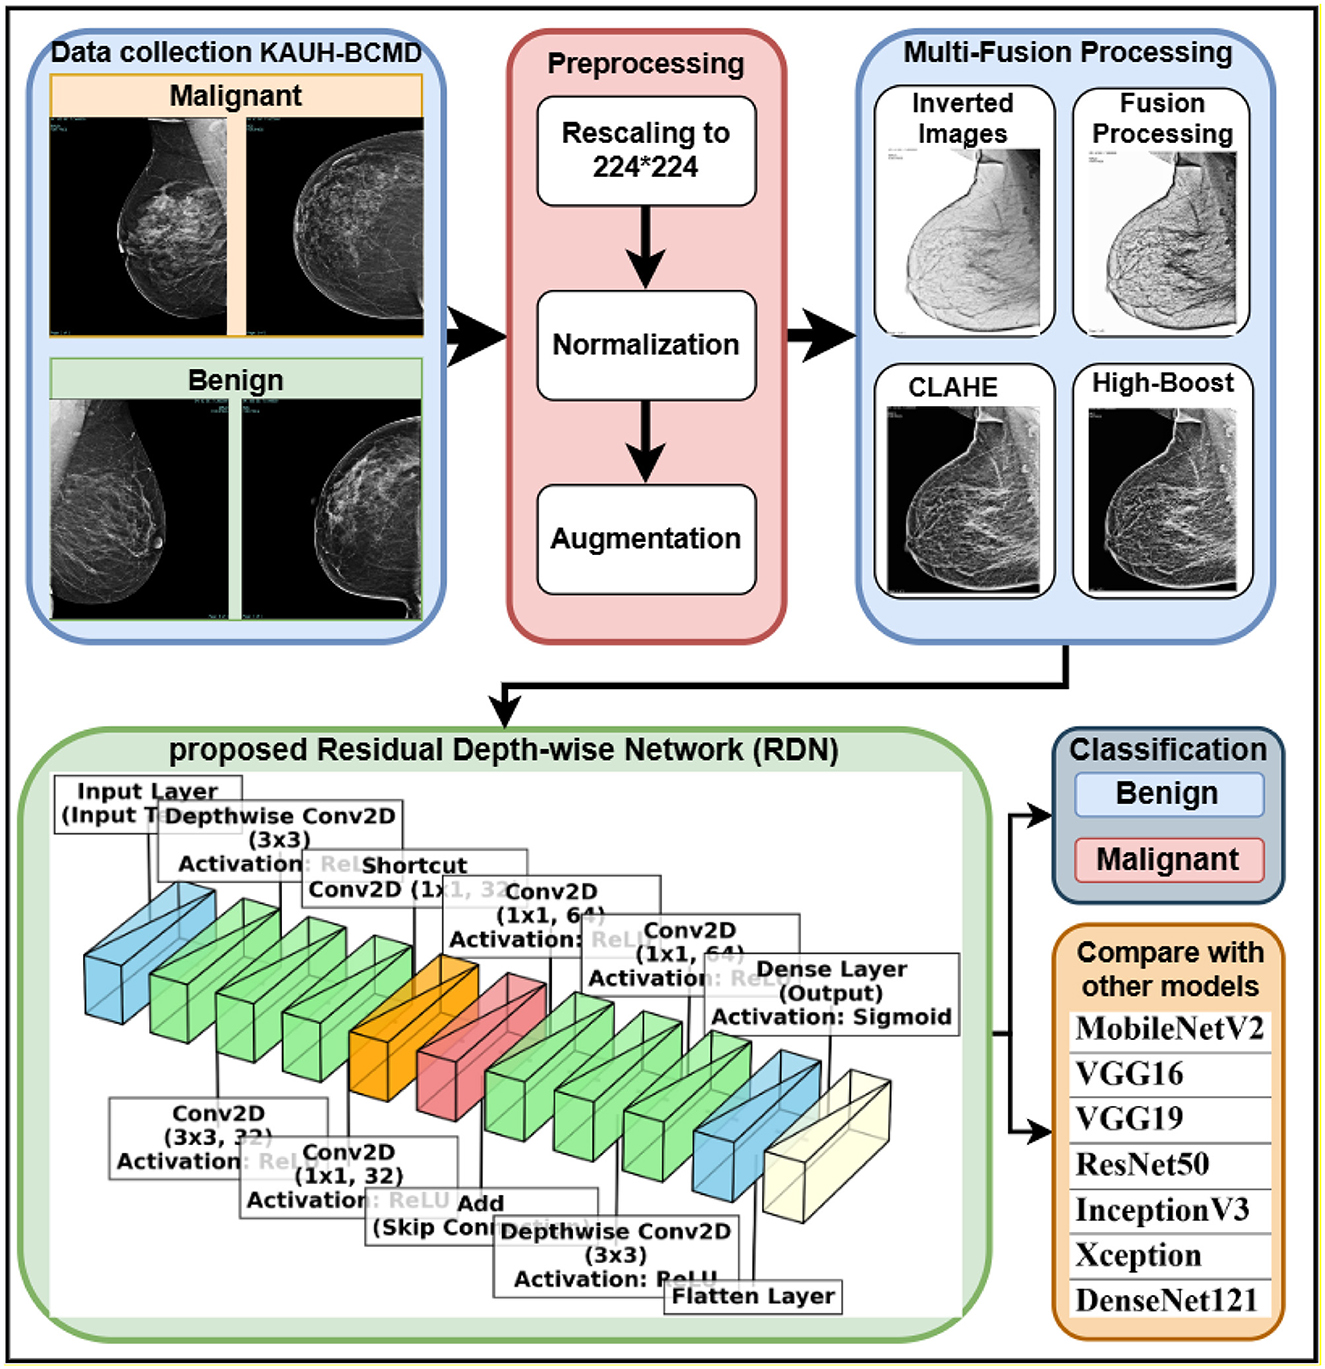

Breast Cancer Treatment (PDQ®) - American Association for。nejmcpc2309499_f1.jpg。Frontiers | (KAUH-BCMD) dataset: advancing mammographic。乳がんに関する最新の情報を提供するモノグラフ。Breast cancer: Know the facts | CNN。病理学や治療法についての詳細な章を含む。。- タイトル: Breast Cancer- 編集者: B. Hoogstraten, I. Burn, H.J. G. Bloom- 出版社: Springer-Verlag- 内容: 乳がんに関する最新の情報を提供するモノグラフ- 特徴: 病理学、診断、治療法についての詳細な章を含む- シリーズ名: UICCご覧いただきありがとうございます。視能検査学。